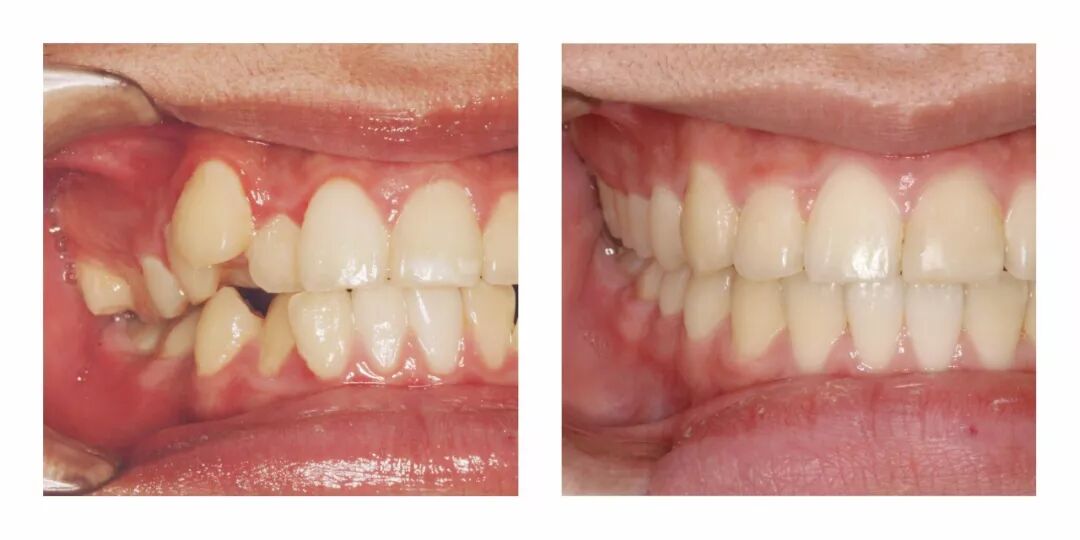

他家有一些具体的正畸案例,效果也很惊人。▼

感觉虽然只是矫正了牙齿,但是整体颜的感觉都不一样了有木有?

从苹果肌到鼻子的形状、下巴的线条,都完全变了啊……▼